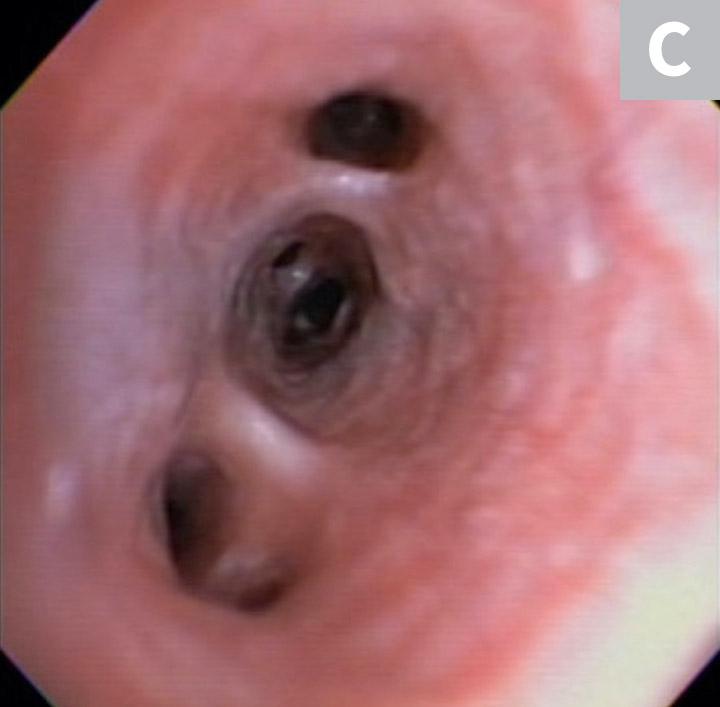

Serum chemistry profile and CBC results were normal, and heartworm antigen test results were negative. Thoracic radiography (right lateral, left lateral, ventrodorsal) revealed a diffuse bronchial pattern but was otherwise unremarkable with no cardiomegaly (vertebral left atrial size, 2.1 [normal, 1.4-2.2]; vertebral heart scale, 9 [normal, 8.7-10.7]) or observable airway collapse (Figure 1). Arterial blood gas showed partial pressure of arterial oxygen 97 mm Hg (normal, 81-103 mm Hg). Echocardiography revealed myxomatous mitral valve degeneration (B1) with no evidence of pulmonary hypertension.2 Laryngoscopy/bronchoscopy showed moderate mucosal irregularity and increased mucus of the lobar bronchi (Figure 2) with normal laryngeal function. Concurrent dynamic bronchial collapse of the left and right mainstem bronchi (grade II/III) was observed (Figure 3).3 Bronchoalveolar lavage was performed and submitted for cytologic evaluation and aerobic culture. Cytology revealed nonseptic neutrophilic inflammation (Figure 4); aerobic culture was negative.

FIGURE 1A

Thickening and mineralization of the airways characteristic of a bronchial pattern and suggestive of chronic airway inflammation